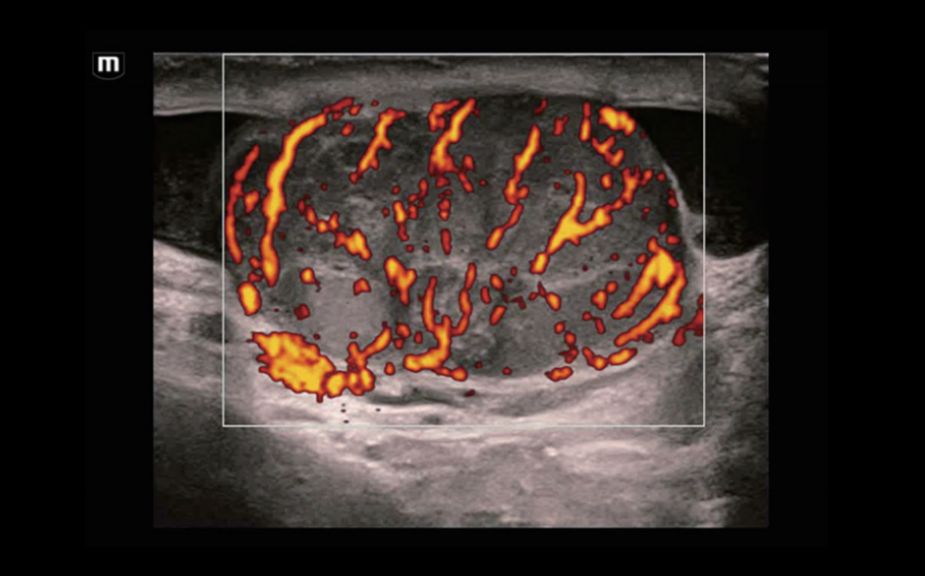

–ö–Θ–Θ–½–‰: –Φ–Β―²–Α―¹―²–Α―²–Η―΅–Β―¹–Κ–Η–Ι ―Ä–Α–Κ –Ω–Β―΅–Β–Ϋ–Η

–ö–Θ–Θ–½–‰: –Ω–Β―Ä―³―É–Ζ–Η―è –Α–¥–Β–Ϋ–Ψ–Φ―΄ ―â–Η―²–Ψ–≤–Η–¥–Ϋ–Ψ–Ι –Ε–Β–Μ–Β–Ζ―΄